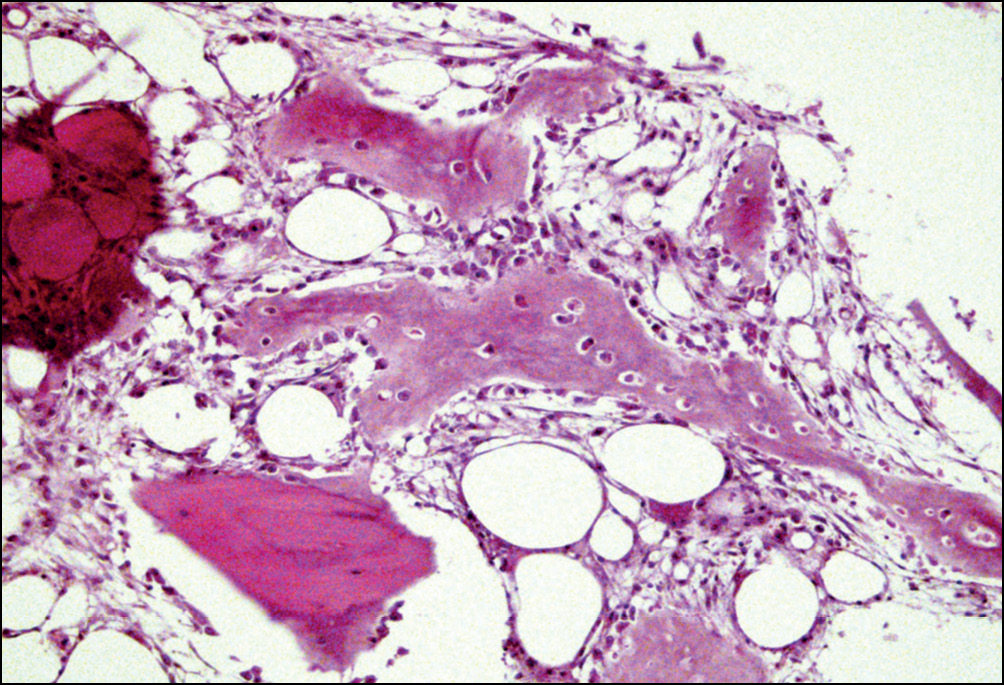

Новообразование костной ткани наблюдали также и вдоль стенки перипротезного канала. Стенка перипротезного канала была представлена клеточно-волокнистой тканью. Во внутреннем слое стенки канала формируются грубоволокнистые костные структуры, которые, по мере созревания, прорастают вниз в виде новообразованных костных балок. В зонах формирования незрелой костной ткани выявляли преобладание отечного основного вещества, имевшего рыхло-волокнистое строение и содержащего множество запустевших тонкостенных сосудов (рис. 2).

Рис. 2. Репаративные изменения костной ткани в зоне перипротезных переломов бедренного компонента. Зона формирования незрелой костной ткани с преобладанием рыхло-волокнистой межуточной ткани, содержащей множество запустевших тонкостенных сосудов. Окраска гематоксилином и эозином. Увел. ×100

Fig. 2. Reparative changes in periprosthetic fractures bone tissue of the femoral component. The zone of formation of immature bone tissue with a predominance of loosely fibrous interstitial tissue containing many neglected thin-walled vessels. Staining with hematoxylin and eosin. Magnification × 100